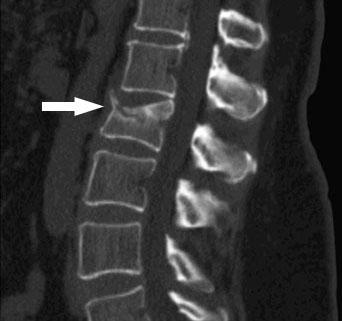

Questa frattura cosiddetta a scoppio di L1 tipologia molto frequente nei traumi spinali da caduta accidentale presenta un frammento osseo proiettato nel canale vertebrale. Si tratta di una condizione più diffusa di quanto si possa credere che interessa persone di tutte le età maggiormente gli anziani che hanno ossa molto deboli. Quando si tratta di frattura di più vertebre non si procede alla somma aritmetica ma si fa una valutazione complessiva.

Esiti di pregressa frattura della L1 con avvallamento della limitante superiore e segni intensi di rimaneggiamento osseo. Dopo una accurata valutazione dei danni presso il nostro Studio in collaborazione con uno specialista neurologo otteneva un risarcimento dallassicurazione di 100000 euro. Frattura corpo per ogni vertebra 800 frattura processo spinoso o processi trasversi dalla lalla vvertebra per ogni vertebra 200 osso sacro frattura corpi vertebrali o base o ali o processi articolari o apice o creste spinali 400 coccige frattura corpi o base o.